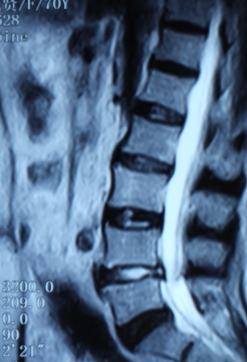

1.患者邹某,男,79岁,因“腰痛双下肢疼痛1年余,加重并间歇性跛行2月”于2014年3月26日入院。入院见患者腰痛病双下肢疼痛、麻木,间歇性跛行,行走约10余米,休息后略缓解。查:直腿抬高试验左40°(+),右55°(+),加强试验(+),腰背伸试验阳性。双侧膝腱未引出,跟腱反射减弱,双侧踇背伸肌力Ⅳ级。入院后诊断为腰椎管狭窄症。患者既往患糖尿病、高血压、冠心病病史。入院后完善检查,明确诊断,请相关科室会诊后认为手术风险极大。经科室讨论后行经皮椎间孔镜下髓核摘除并椎管扩大成形术,手术麻醉方式为局麻。于2014年3月29日行手术治疗,经椎间孔入路椎间孔镜下髓核摘除椎管扩大成形术。手术顺利,术中无出血,手术时间约40min。术中可与患者交流。术后患者即可感双下肢无疼痛,第二天佩戴腰围下地活动后双下肢无不适。术后半年复查腰椎MRI示突出髓核已摘除,神经根无受压。术后随访1年,患者目前病情恢复良好,无下肢疼痛、麻木,无间歇性跛行。

术前腰椎MRI